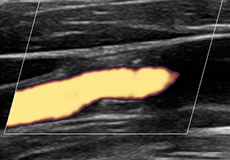

図:内頚動脈のプラーク

頚動脈超音波検査頚動脈の内膜中膜の肥厚は動脈硬化と相関します。当院でも頚動脈壁肥厚の強い無症状の患者さんを二次検査へ紹介することで、強い心血管の狭窄や脳血管の狭窄、下肢動脈狭窄を発見し、大事に至る前にそれらの治療へ結びつけています。